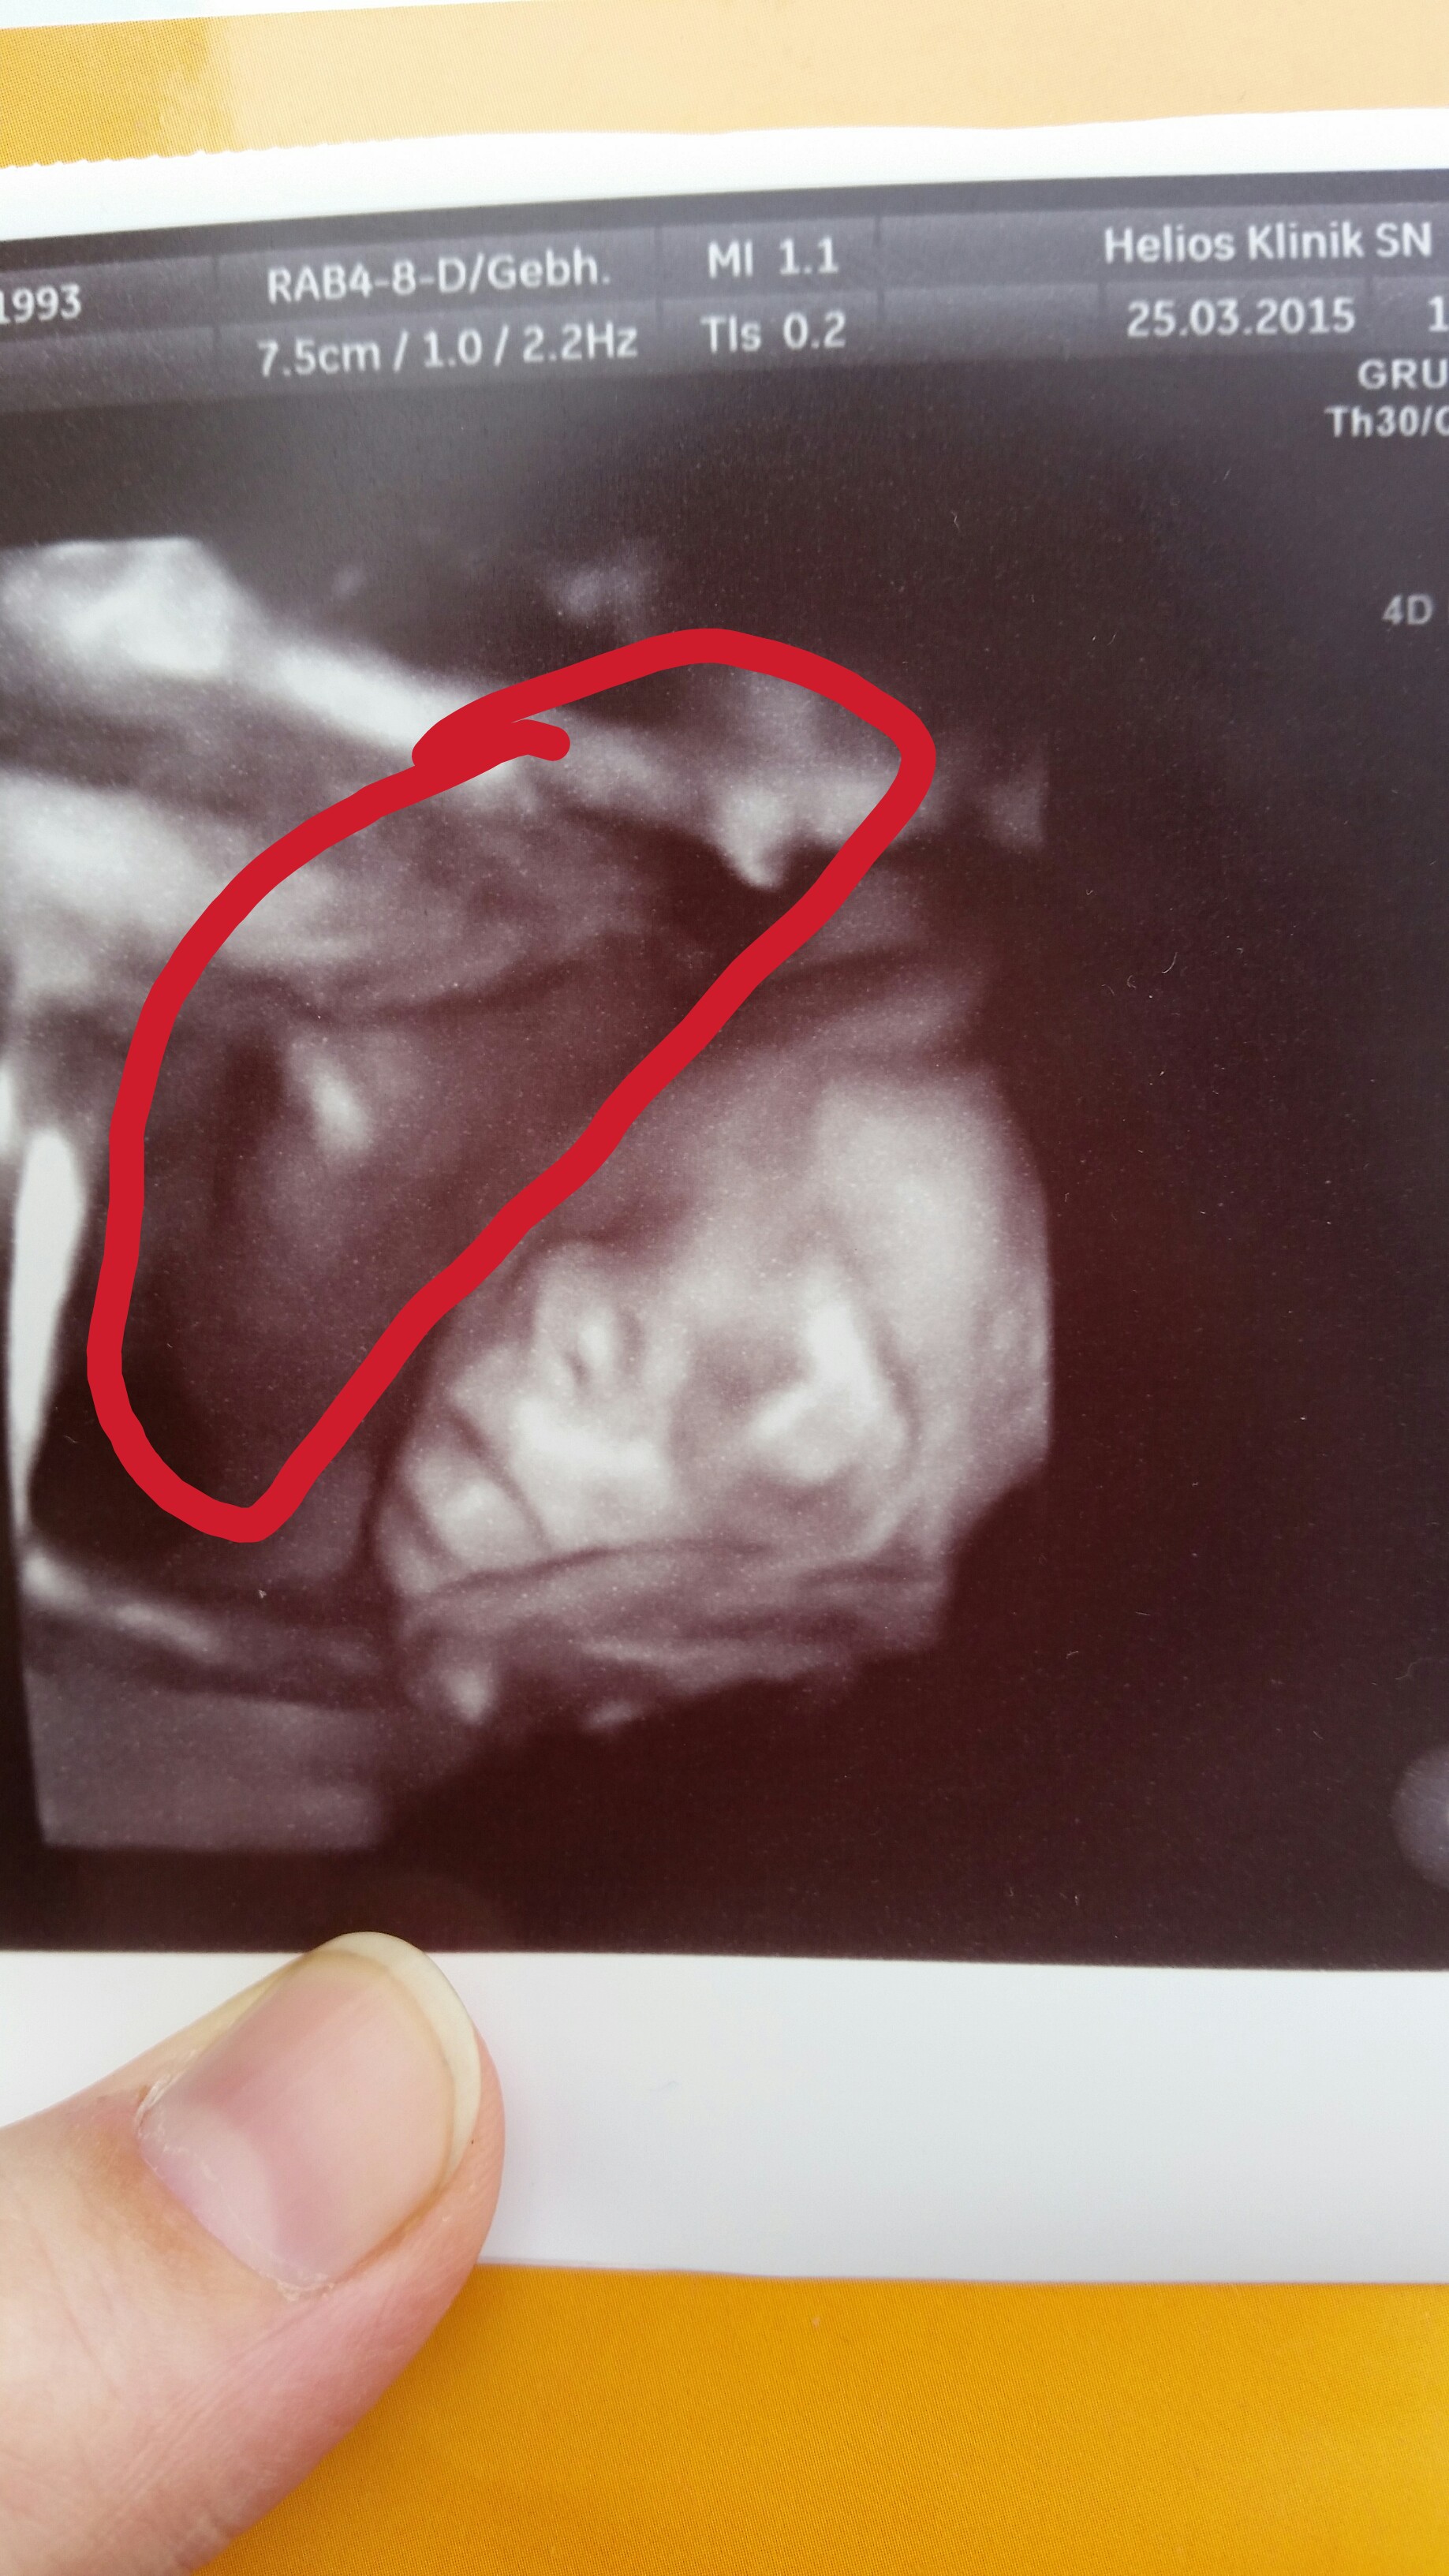

14 Ssw 3d Und 4d Ultraschall Zwillinge Leidenschaft Leben Lieben Lernen

Zwillinge Schwangerschaftswoche 8 In 4d Youtube